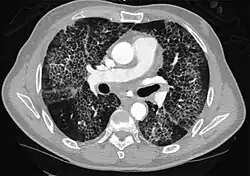

High-resolution CT image showing ground-glass opacities in the periphery of both lungs in a patient with COVID-19 (red arrows). The adjacent normal lung tissue with lower attenuation appears as darker areas.

Ground-glass opacity is among the most common imaging findings in patients with confirmed COVID-19.[16][17] One systematic review found that among patients with COVID-19 and abnormal lung findings on CT, greater than 80% had GGOs, with greater than 50% having mixed GGOs and consolidation.[16] GGOs with mixed consolidation has most often been found in elderly populations.[18] Several studies have described a pattern among initial, intermediate, and hospital discharge imaging findings in the disease course of COVID-19. Most commonly, initial CT imaging reveals bilateral GGOs at the periphery of the lungs. During initial stages, this is most often found in the lower lobes, although involvement of the upper lobes and right middle lobe has also been reported early in the disease course.[16][18] This is in contrast to the two similar coronaviruses, SARS and MERS, which more commonly involve only one lung on initial imaging.[19][20] As the COVID-19 infection progresses, GGOs typically become more diffuse and often progress to consolidation.[11][18] This is sometimes accompanied by the development of a crazy paving pattern and interlobular septal thickening.[18] In many cases the most severe pulmonary CT abnormalities occurred within 2 weeks after symptoms began.[17] At this point, many individuals begin showing resolution of consolidation and GGOs as symptoms improve. However, some patients have worsening symptoms and imaging findings, with further increase in septal thickening, GGOs, and consolidation. These patients may develop lung "white-out" with progression to acute respiratory distress syndrome (ARDS) requiring treatment escalation.[17][21]